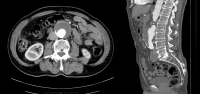

Exemplo de vídeo:

- AAA infrarrenal, diâmetro 54,2 mm

- aneurisma da artéria ilíaca comum direita, diâmetro 41,1 mm